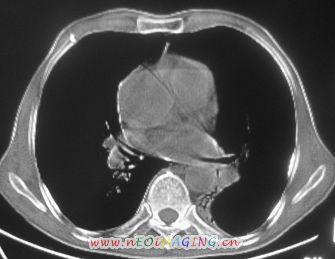

以下是引用卜一在2007-10-7 9:38:00的发言:[br]左下肺胸膜下团片影,内见含气支气管像,临近胸膜未见增厚。多考虑:1 左下肺炎症,建议消炎后复查!2 不除外肺隔离症合并感染!